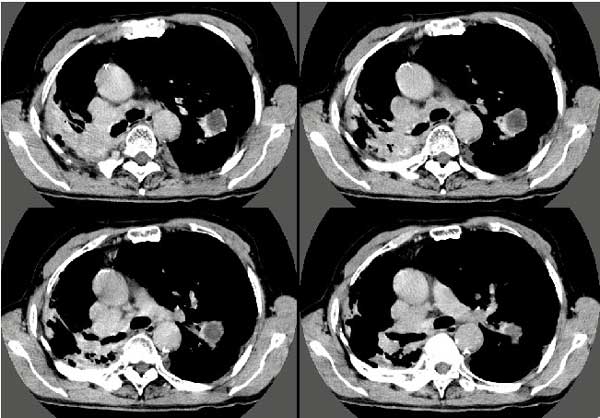

以下是引用扬仪在2005-5-12 20:46:40的发言:[br]右肺呈术后改变;双侧肺野散在分布斑片状、点状高密度病灶,(似可见“树芽征”);左上尖后段见斑团状高密度病灶(2个层面?),边缘毛糙,段性分布,与斜裂相邻,临近胸膜粘连;增强示病灶边缘强化,内呈水样密度;心影、纵隔右移,内可见4r淋巴结肿大。[br]意见:1、双肺继发性肺结核,左上为干酪病灶;[br] 2、矽肺合并感染;[br] 3、建议抗痨+抗炎。 [br]愚人之见,请高人指教!